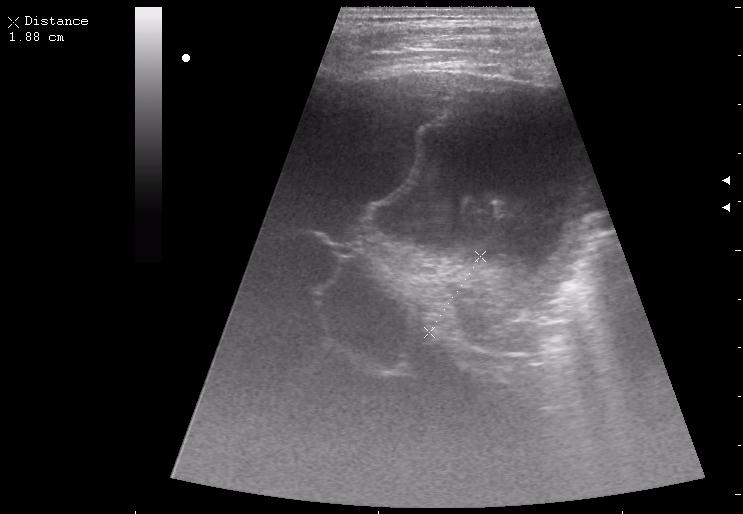

сегментарная пневмония. Экссудативный плеврит.

30788.JPG